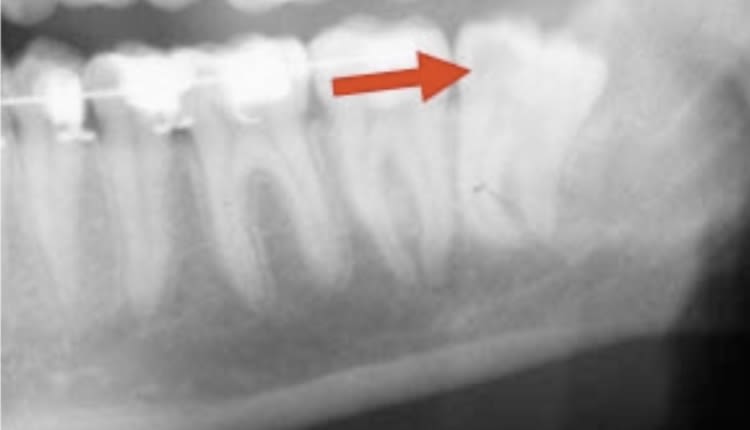

Bien sur Junior , il faut enlever la dds , et apres la 7 ?

Tu n as jamais remarque , qu apres ortho ,les 7 ne sont pas a leurs place ?

Elles sont souvent basses et non allignees

" Elles sont souvent basses et non allignees "( les 7 )

Et si les 7 etaient bien à leur place prevues ? Hein finalement ?

C 'est ca la magie du nivellement :-))

Tu vois ou je veux en venir ?

Tu comprends mieux l histoire des meubles :-))) ?